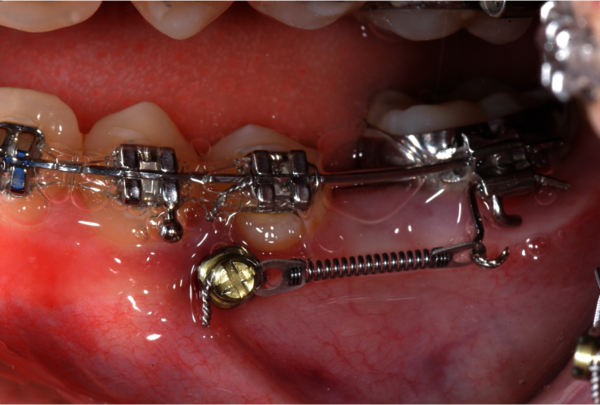

Zahn-Freilegung

Eine Zahnfreilegung ist eine (manchmal sehr kleine) Operation die dann durchgeführt wird, wenn ein oder mehrere Zähne an einem natürlichen Zahndurchbruch verhindert werden, somit bleibende Zähne nicht von allein an ihren regulären Platz in der Zahnreihe gelangen. Es handelt sich in der Regel um einen gesunden, eigenen Zahn der noch im Kieferknochen versteckt ist. Bei dieser OP wird der Zahn durch uns freigelegt und mit einem kleinen Metallplättchen (Bracket/Zugkette) beklebt und später durch die/den Kieferorthopäden/-in zum Einwandern in die Zahnreihe gebracht.

Zahnfreilegung mit Zugkette